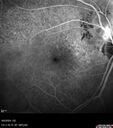

Peripapillary CNVM No Treatment20 views85 year old with peripapillary CNVM watched for many years.